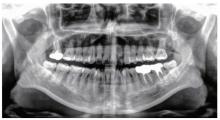

Figure 1

Preoperative and postoperative periapical radiographs of the mandibular left first molar (36) A, preoperative periapical radiolucency showing well-defined radiopaque mass with radiolucent border; B, postoperative radiograph of completed root filling; C and D, 3-month and 6-month follow-up X-ray."